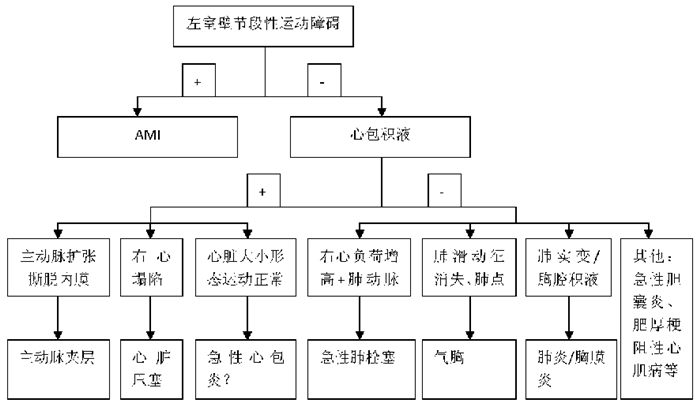

3.5.2 急性胸痛的常见病因的超声影像特点引起致命性胸痛的病因包括:(1)急性心肌梗死 早期即可表现室壁节段性运动异常,心肌回声可减低或变化不明显(详见2.1章节)。(2)主动脉夹层 直接征象为撕脱主动脉内膜呈带/线状漂浮摆动,间接征象包括升主动脉根部增宽、心包积液、心脏压塞和主动脉瓣反流(详见2.1章节)。(3)其他致命性胸痛 包括张力性气胸、肺栓塞,详见创伤及急性呼吸困难相关章节。

3.5.3 胸痛的超声诊断流程(图 39) |

首先观察室壁运动,室壁节段性运动障碍高度提示急性心肌梗死[33],但应除外脓毒症休克导致的心肌顿抑。若无节段性运动障碍,第二步观察有无心包积液,存在心包积液者:①伴主动脉扩张、内膜撕脱,提示主动脉夹层[33, 34];②伴右心塌陷,提示心脏压塞;③心脏大小、形态及运动正常,结合临床鉴别急性心包炎。无心包积液时,按以下顺序逐步排查[35, 36]:①右心负荷增加及肺动脉高压表现,提示肺栓塞[37, 38];②行肺部超声检查观察肺滑动,存在肺滑动并可探及胸腔积液和/或肺实变,提示急性胸膜炎和/或肺炎;肺滑动消失并可探及肺点提示气胸;未探及肺点但可观察到肺实变或B+线提示肺炎伴胸膜粘连;③观察肋骨皮质连续性,排除肋骨骨折。此外急性胸痛病因还包括急腹症[39, 40]、带状疱疹、肋间神经炎、肋软骨炎、食管裂孔疝、神经官能症等,需根据病史、临床表现及其他辅助检查综合判断。